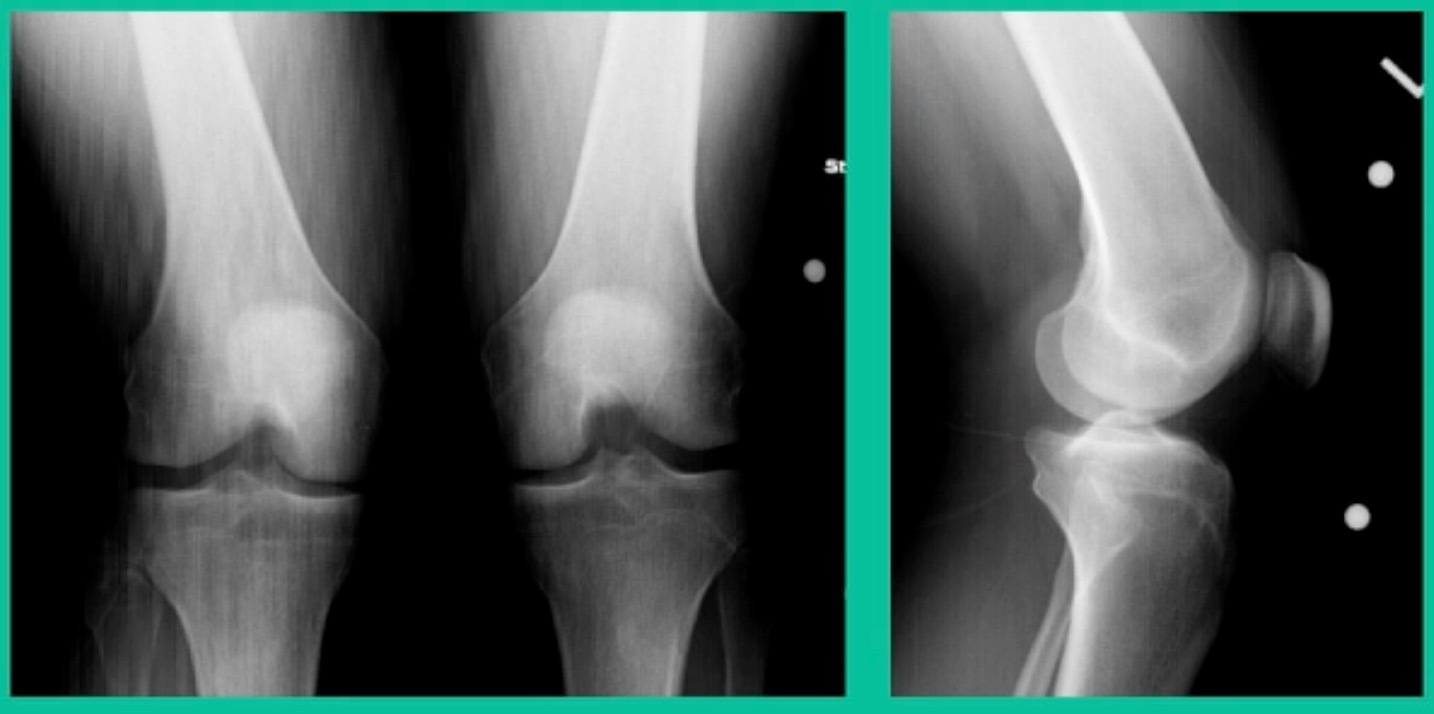

Another case example. 14-year-old male tennis player, 10 months of knee pain (Figure 7A).

This is a Trochlear defect (Figure 7B).

This goes back to metallic screw fixation, because this one is macroscopically unstable. That is a fracture non-union. That’s an atrophic non-union. Debride it, curette it, drill it, and thenwe use metal screws because it’s macroscopically unstable.

However, in this instance, we did take the screws out.

He was back to everything at 16 weeks and, at two years, he had no further symptoms. How do these do? There’s plenty of literature that shows that metallic screw fixation for unstable OCD, not just in juveniles, but in adults, will lead to reliable fixation. It’s a four-month process. They get back to everything, and they rarely have problems downstream.

Now, we’ll shift to the adult. This is a 27-year-old. Right knee swelling, activity-related, and classic failed nonsurgical treatment on the lateral side of the knee.

This will probably be fixed. It’s a big piece and we’ll try to preserve it. The literature shows that preservation does pretty well. In this instance, there’s very little bone. It’s somewhat dystrophic, not very encouraging in my mind.

We removed it, and you say, “Well, this is terrible.” Lateral side, how is he going to do? Interestingly, the natural history does not suggest that that person will do badly. Probably the worst ones are going to be the ones who fall off to the side into the trochlea and lateral meniscus.